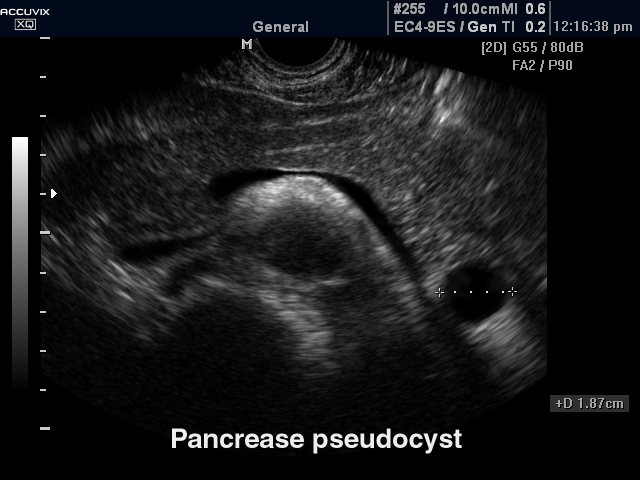

Возникновение очаговых диффузных изменений в органе свидетельствуют о том, что в нем развиваются камни, кисты или происходит опухолевый процесс. И ткани железы могут иметь очаговые или местные поражения. Диффузные изменения в организме требуют дополнительного клинического проведения обследования и комплексного лечения.